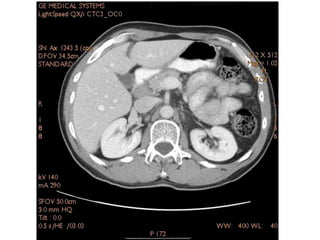

Tomografia do Abdome